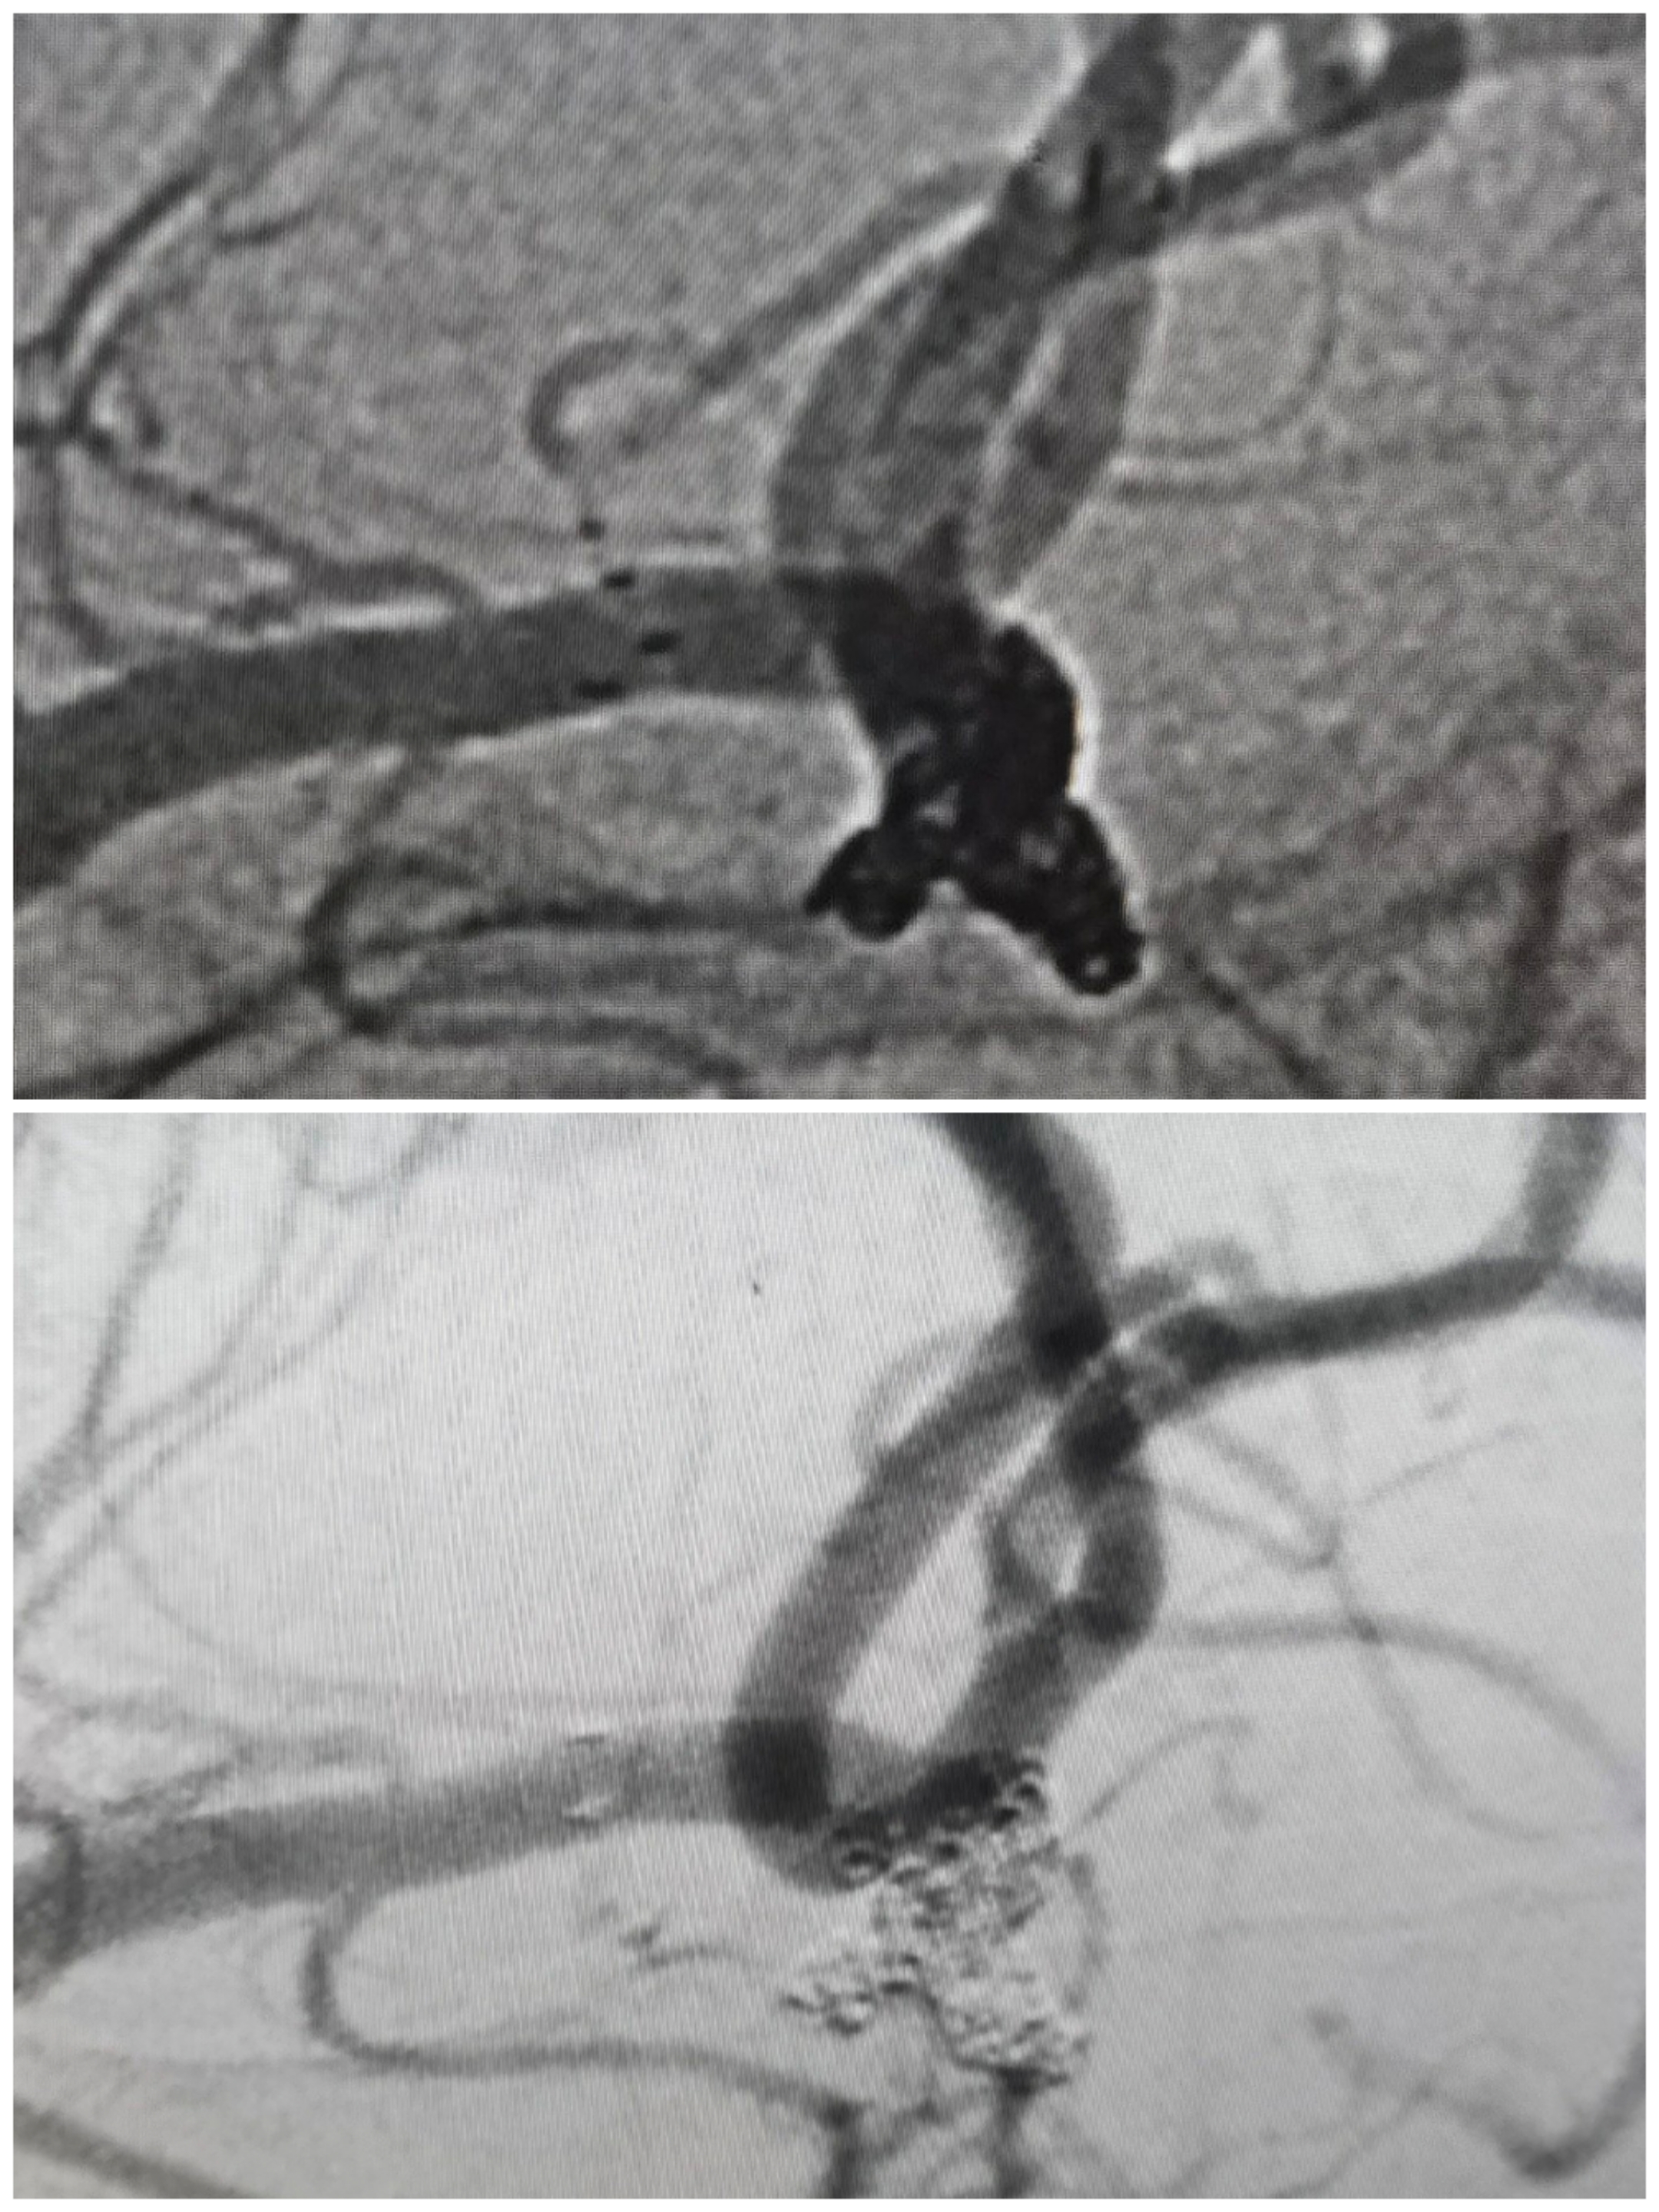

病例1大脑中AN支架甩尾辅助栓塞

SAH入院,Hunt-Hess分级2级,

CTA提示不规则分叉部、多分叶、动脉瘤,瘤颈波及上干为主

术前造影

3D重建情况